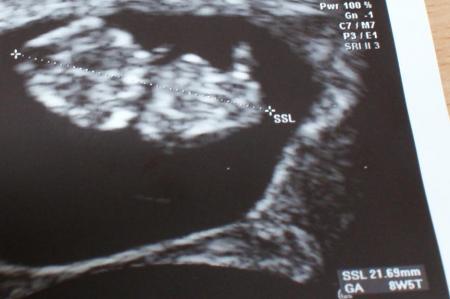

so nun stelle ich mal die zwei bilder rein. 1. bild 16.04. 9,48mm

Bild zu us Bild vom 16.04 und 30.04.2010 - Forum für November - Mamis